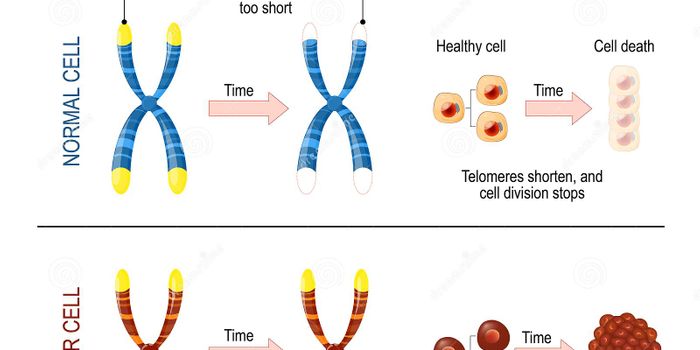

MAR 16, 2021Clinical & Molecular DXIn 2012, a United Nations report estimated that there are over 316,000 people worldwide over the age of 100. What’ ...

FEB 21, 2023Cell & Molecular BiologyThe Griffith Lab at UNC discovered telomeric protein & potential biomarker VR (green), shown in the nuclei (blue) of hum ...

DEC 16, 2015Clinical & Molecular DXOur society is fascinated by youth and aging. But while some people are on a quest for the “magic” youth cre ...